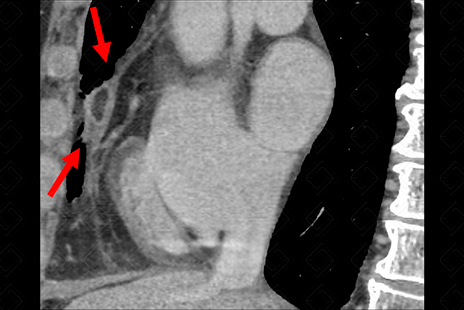

Texto alternativo para a imagem Créditos: Dra. Elazir Mota - Rio de Janeiro/RJ

Descrição das imagens: Tomografia computadorizada do tórax, janela de mediastino. Observa-se lesão ovalada, com densidade de gordura no seu interior (setas vermelhas), associada a espessamento do pericárdio (seta amarela), em paciente com dor torácica aguda, compatível com necrose da gordura epipericárdica.

• Tomografia computadorizada de tórax: Observamos uma imagem arredondada, encapsulada, com densidade de gordura, podendo ou não estar associado a espessamento do pericárdio e, até mesmo, derrame pleural.